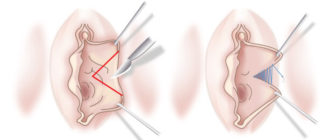

Как должны выглядеть здоровые половые губы Современные женщины направляют все силы на поддержание красивой